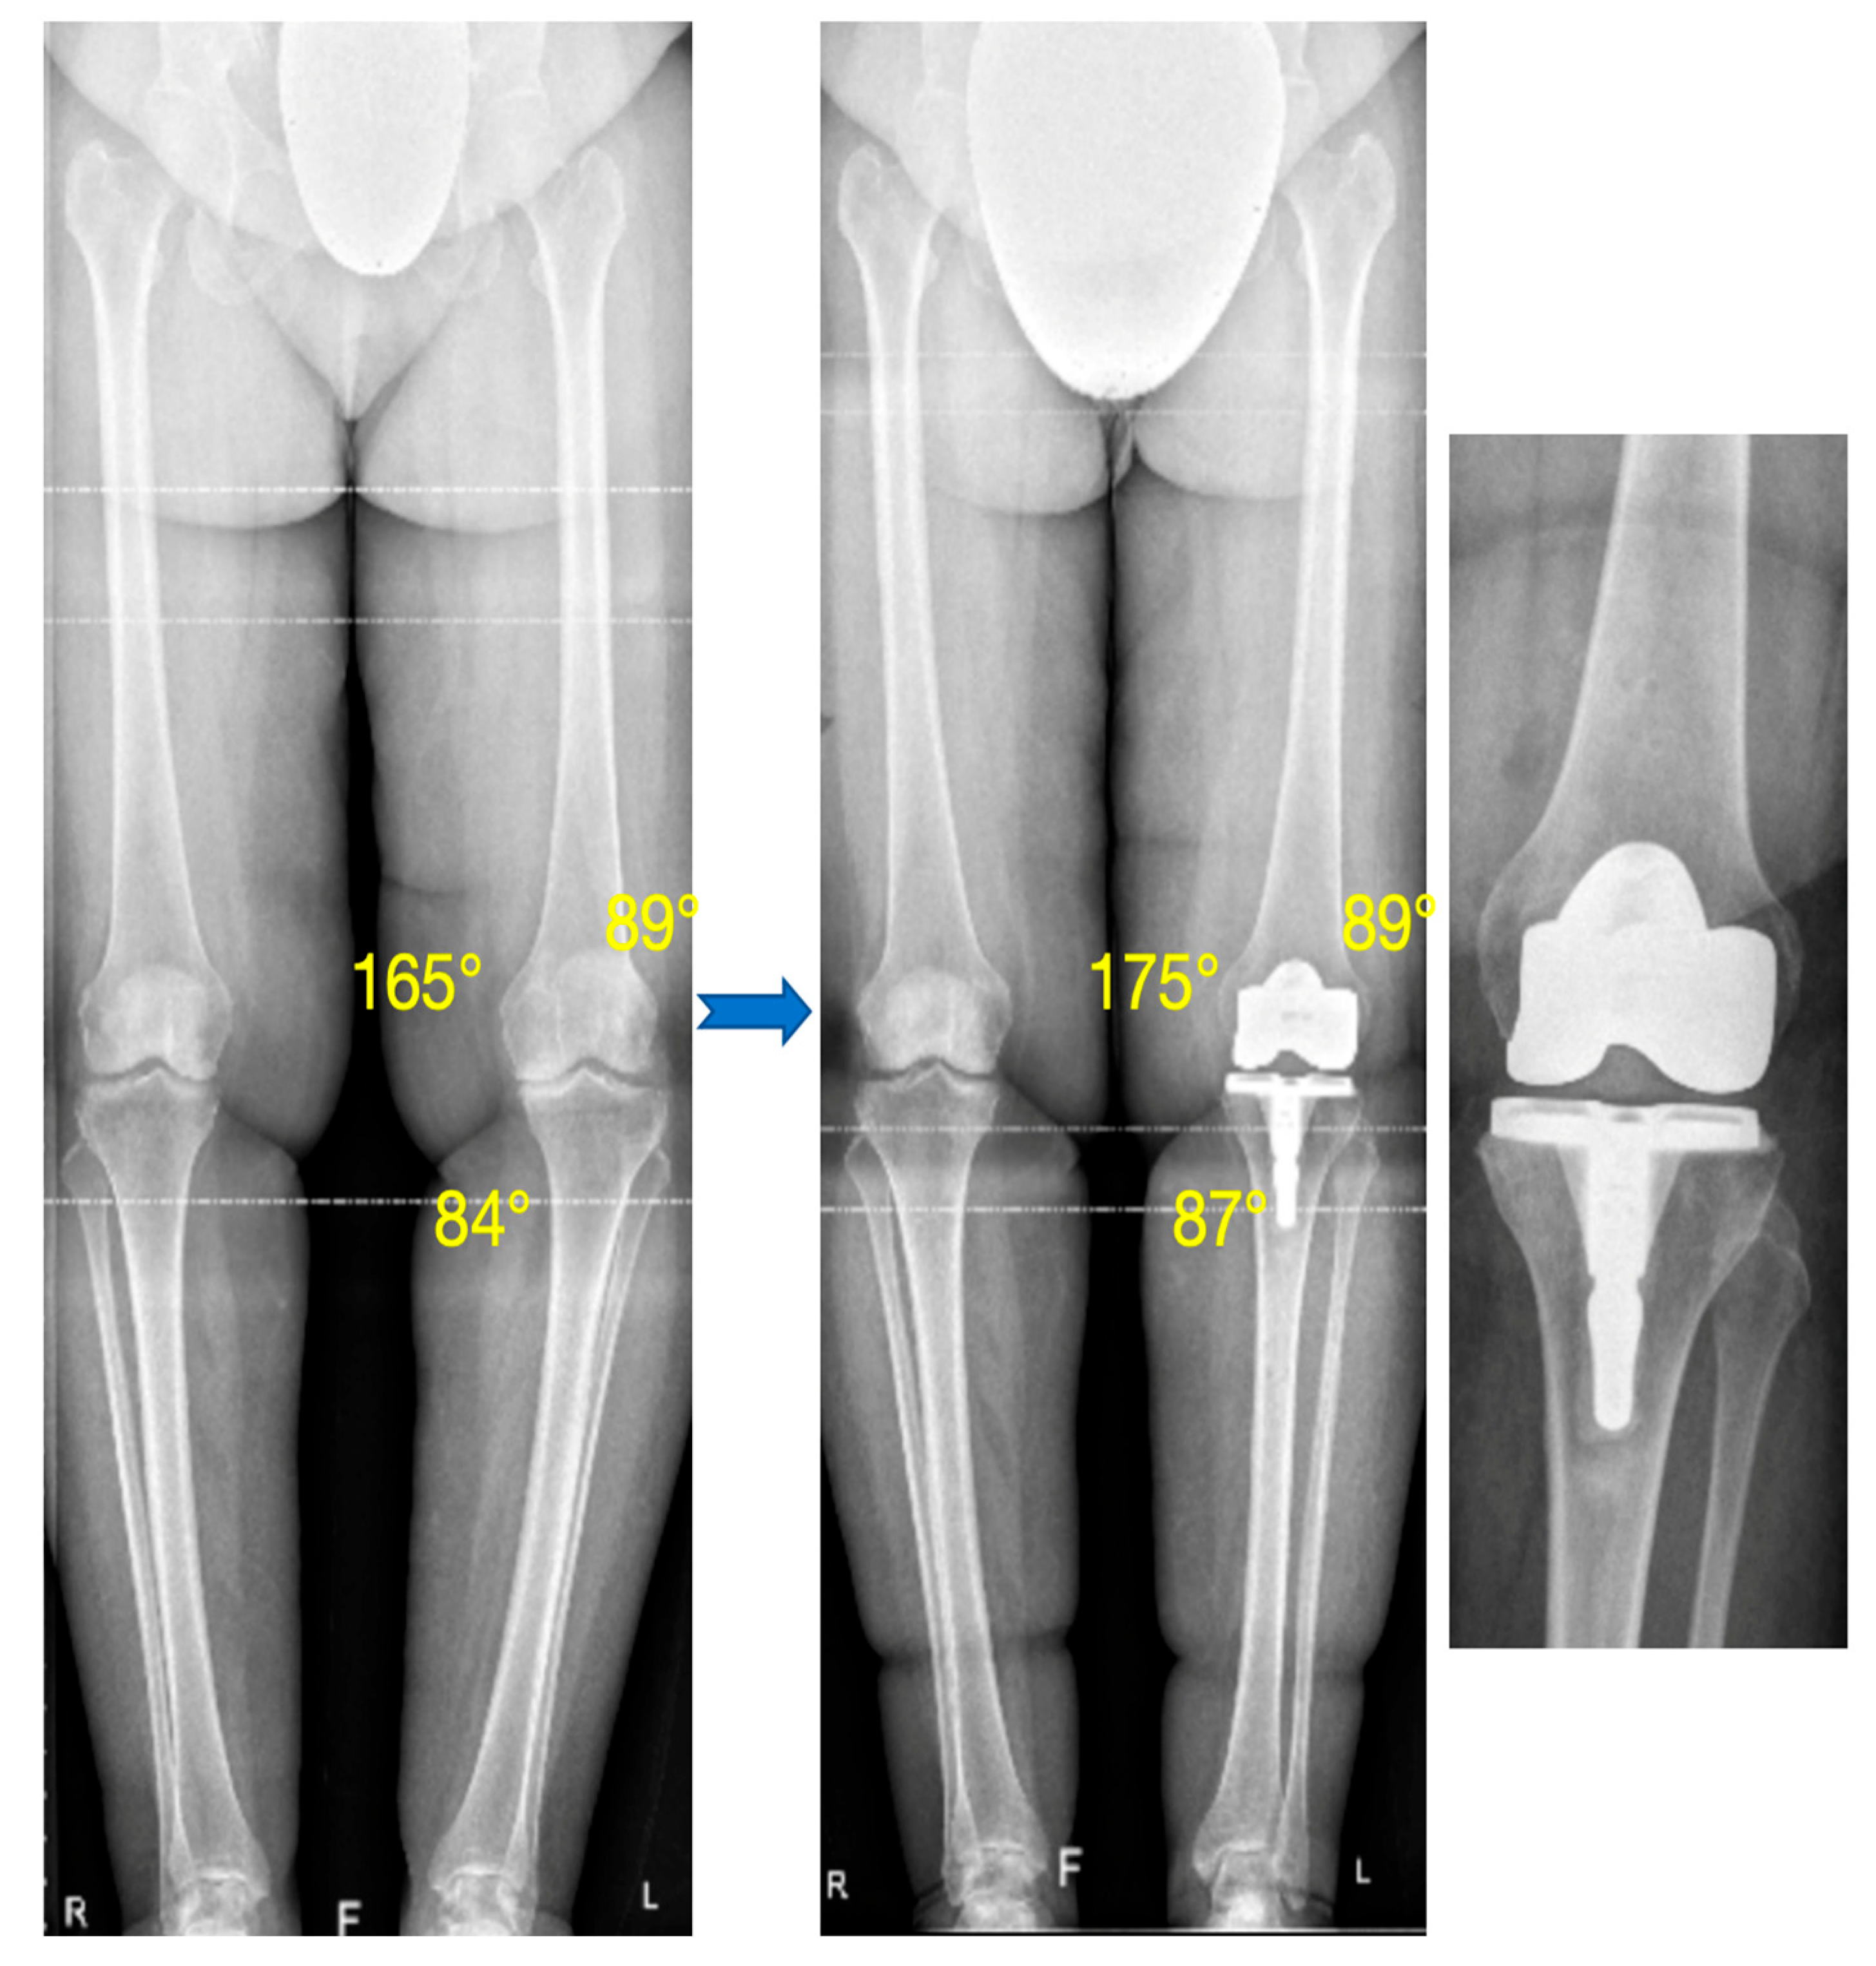

3.1. Alignment

| HKA (°) (mean ± SD) [Min; Max] | 170.2 ± 3.9 [163.5; 179] | 177.4 ± 2.2 [172; 182] | <0.0001 |

| OUTLIERS: HKA < 175° | - | 4 (8.9%) | - |

| mMDFA (°) (mean ± SD) [Min; Max] | 91.3 ± 2 [87; 94] | 91.1 ± 1.5 [88; 94] | 0.76 |

| OUTLIERS: mMDFA > 95° | - | 0 | - |

| OUTLIERS: mMDFA > 93° | - | 1 (2.2%) | - |

| MPTA (°) (mean ± SD) [Min; Max] | 85.7 ± 2.1 [82; 90] | 87.4 ± 1.8 [83; 90] | <0.0001 |

| OUTLIERS: MPTA < 85° | - | 2 (4.4%) | - |

| OUTLIERS: MPTA < 87° | - | 11 (24.4%) | - |

| JLCA (°) (mean ± SD) [Min; Max] | 6.2 ± 2.2 [1; 12] | - | - |

| JLO (°) (mean ± SD) [Min; Max] | −0.9 ± 2.4 [−7; 5] | 0.9 ± 1.7 [−2; 4] | 0.0002 |

| OUTLIERS JLO > 3° | - | 3 (6.7%) | - |

| Slope (°) (mean ± SD) [Min; Max] | 81.7 ± 3.1 [74; 89] | 86.8 ± 1.8 [83; 91] | <0.0001 |

| OUTLIERS Slope < 80° | - | 0 | - |

| Difference Post–Pre of Posterior Femoral offset (mm) (mean ± SD) [Min; Max] | 1.9 ± 1 [0.09; 5.4] | - |